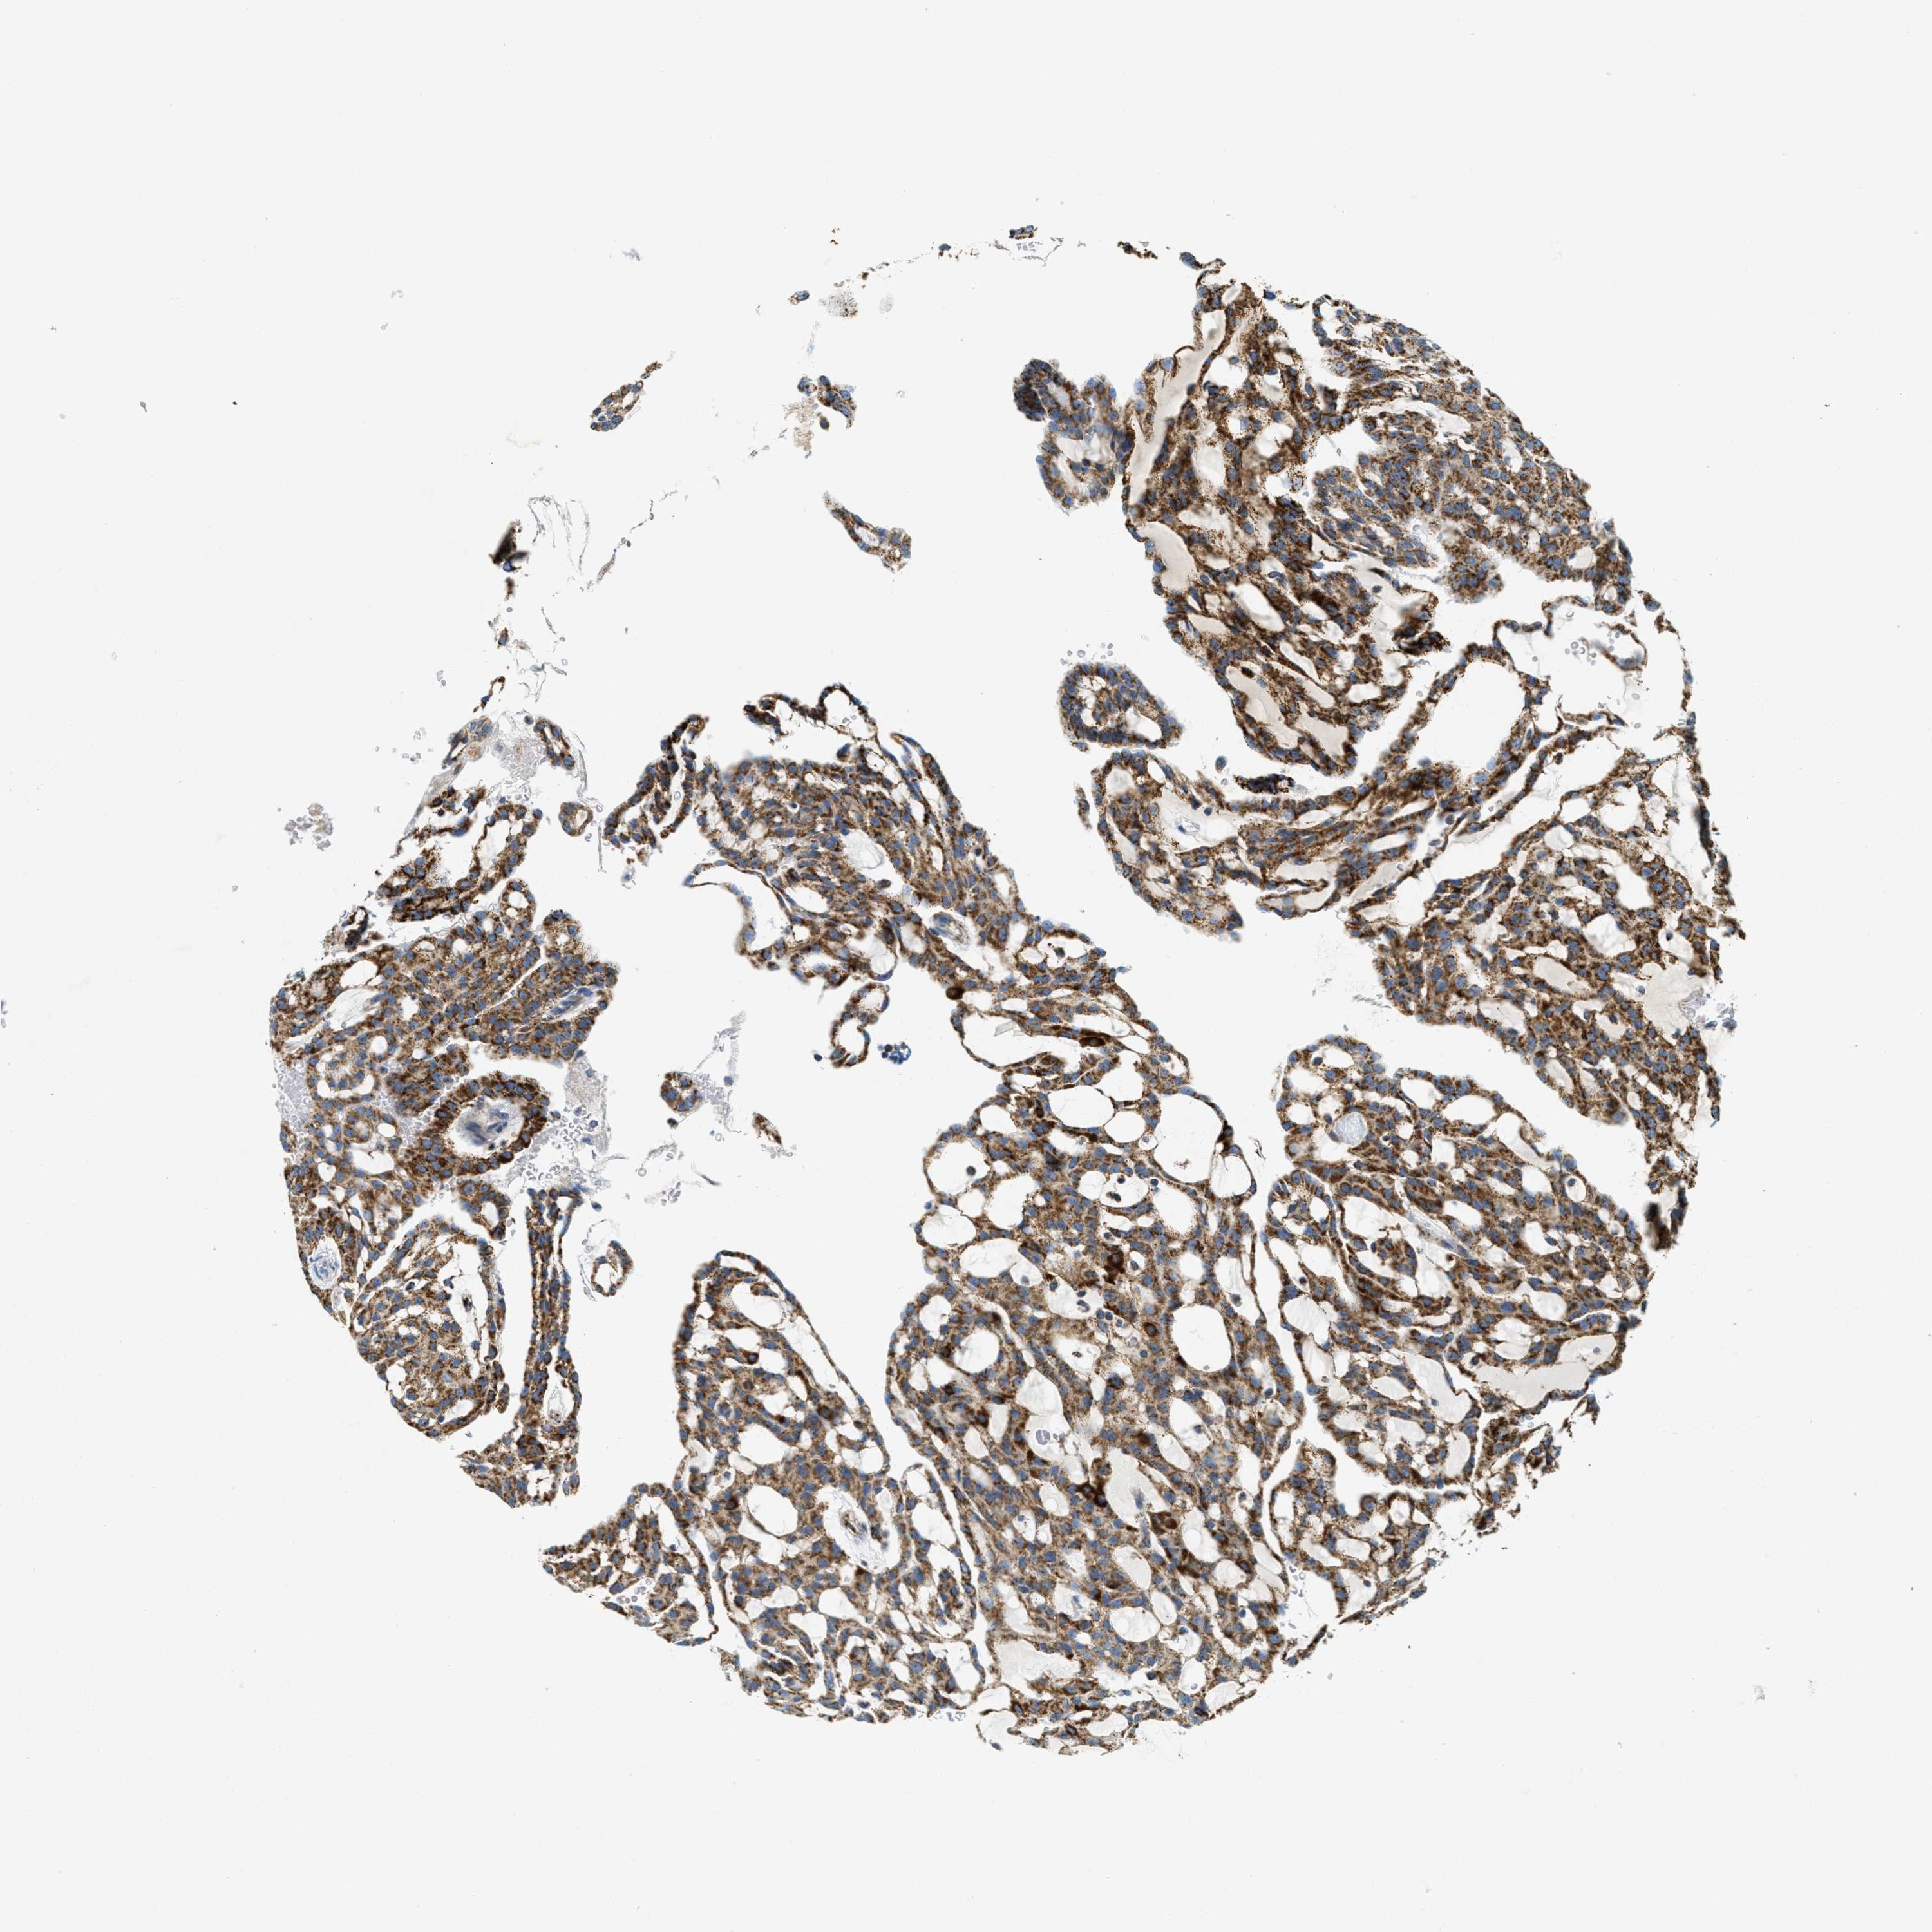

KIDNEY RENAL PAPILLARY CELL CARCINOMA (TCGA) - Interactive survival scatter ploti

The Survival Scatter plot shows the clinical status (i.e. dead or alive) for all individuals in the patient cohort, based on the same data that underlies the corresponding Kaplan-Meier plots. Patients that are alive at last time for follow-up are shown in blue and patients who have died during the study are shown in red.

The x-axis shows the expression levels (FPKM) of the investigated gene in the tumor tissue at the time of diagnosis. The y-axis shows the follow-up time after diagnosis (years). Both axes are complimented with kernel density curves demonstrating the data density over the axes. The top density plot shows the expression levels (FPKM) distribution among dead (red) and alive patients (blue). The right density plot shows the data density of the survived years of dead patients with high and low expression levels respectively, stratified using the cutoff indicated by the vertical dashed line through the Survival Scatter plot. This cutoff is automatically defined based on the FPKM cutoff that minimizes the p-score. The cutoff can be changed by dragging the vertical line or by entering a cutoff value in the square labeled "Current cut-off".

Under the Survival Scatter plot the p-score landscape (black curve; left axis) is shown together with dead median separation (red curve; right axis). Dead median separation is the difference in median mRNA expression between patients who have died with high and low expression, respectively. It is calculated as follows: median FPKM expression of dead patients with high expression - median FPKM expression of dead patients with low expression. This is intended to aid the user in visually exploring custom cutoffs and the associated p-scores and dead median separation.

Individual patient data is displayed and can be filtered by clicking on one or more of the category buttons on the top of the page. Categories describing expression level and patient information include: high, low, alive, dead, female, male and tumor stages. The scale of the x-axis can be toggled between linear and log-scale by clicking on the "x log" button. Mouse-over function shows TCGA ID, patient information and mRNA expression (FPKM) for each patient.

& Survival analysisi

Kaplan-Meier plots summarize results from analysis of correlation between mRNA expression level and patient survival. Patients were divided based on level of expression into one of the two groups "low" (under cut off) or "high" (over cut off). X-axis shows time for survival (years) and y-axis shows the probability of survival, where 1.0 corresponds to 100 percent.

HLCS is not prognostic in Kidney Renal Papillary Cell Carcinoma (TCGA)